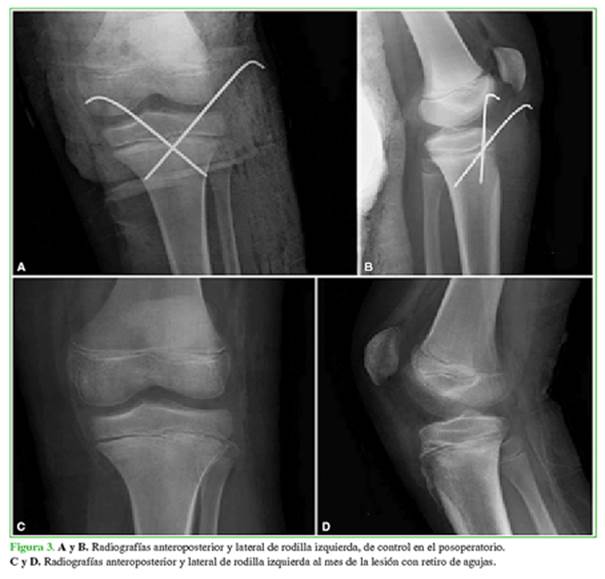

Se solicitaron radiografías anteroposterior y lateral de rodilla izquierda, en las que se apreciaba una epifisiólisis tipo I de Salter-Harris, y tipo IV-A de la clasificación de Ryu y Debenham3 (Figura 1). Tras informar al paciente y a los padres se decidió el tratamiento quirúrgico urgente. Se procedió a la reducción cerrada de la fractura y la fijación con dos agujas de Kirschner (Figura 2). No había inestabilidad en la rodilla. La evaluación detectó la presencia de pulsos distales y el examen con oxímetro de pulso también arrojó valores dentro de la normalidad. Se inmovilizó con una férula inguinopédica.

Cuando el paciente se recuperó de la anestesia, el dolor había mejorado y la movilidad de los dedos no era dolorosa. La inmovilización se mantuvo durante cuatro semanas y no se permitió la carga. Posteriormente se retiraron la inmovilización y las agujas, y se permitió la flexo-extensión libre y la marcha protegida con bastones durante dos semanas más (Figura 3).